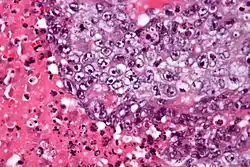

Description de l'image Embryonal carcinoma - very high mag - cropped.jpg.

Le carcinome embryonnaire est un type de tumeur germinale peu commun qui se produit dans les ovaires et les testicules[1]. On peut aussi la retrouver sous le nom de tumeur vitelline ou tumeur du sinus endodermique du testicule et de l'ovaire[2].